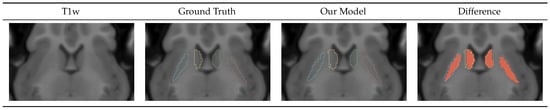

4.1.3. Caudate-Putamen Segmentation Mask

Figure 4 shows a portion of an axial slice of the input T1w image, the ground truth manual segmentation, our Seg model prediction, and the difference between them. In the T1w image, we can see that the caudate and putamen regions are very hard to distinguish, requiring an expert to label them correctly. We can see that although the boundaries of the predicted regions varied from the ground truth, our model prediction was very close to the ground truth. In the qualitative analysis, we observed that the Seg model tended to over-segment the regions. Table 5 shows the metrics for the Seg model performance on the test dataset. We can see that all regions had a similar DICE score of 0.8 and a bAVD of around 0.28 voxels. The model was consistent on the Iowa dataset, with a standard deviation under 0.05 for the DICE for all classes and a standard deviation of 0.06 voxels for the bAVD. The model consistency on the German dataset was slightly worse, as indicated by the standard deviation of 0.15 voxels for the bAVD and 0.07 for the DICE for the left putamen. We believe this was due to the worse image quality of the German T2w images.

Figure 4.

Caudate-putamen segmentation mask visualization. The difference image shows the ground truth mask in red with the color outline of our model prediction. The mask generated by our model closely resembles the manually traced ground truth label.